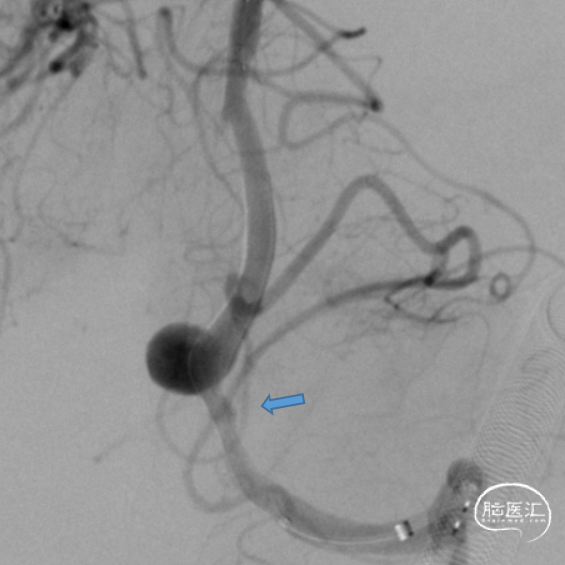

处理后

术后正侧位造影。